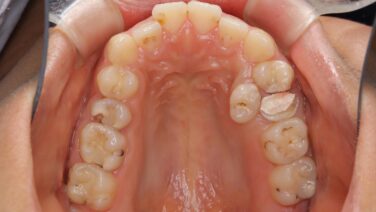

なんG なんG虫歯じゃなくても歯医者に行く部